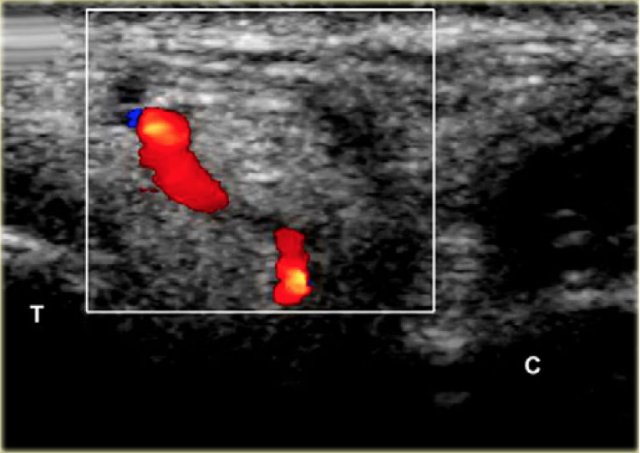

US-guided injection of the sinus tarsi at the right-hand side with a lateral approach. The transducer is held in a coronal oblique plane. The needle is introduced along the long axis of the transducer.

The sinus tarsi can easily be visualized using ultrasound.

The patient turns onto the contralateral side laying the foot to be treated with its medial surface against the table top, the lateral side of the foot being uppermost.

The transducer is held in a coronaloblique plane with regards to the foot.

The sinus tarsi is identified as a triangular space between the anterior process of the calcaneus and the talar neck.

The tip of the needle (arrow head) is seen within the cone shaped sinus tarsi, which is bordered by the talus (T) and calcaneus (C).

Depending on the degree of inflammation there may be hyperemia of the space and there may be intervening vessels visible, which one wishes to avoid. This is relatively easy, especially with colour doppler